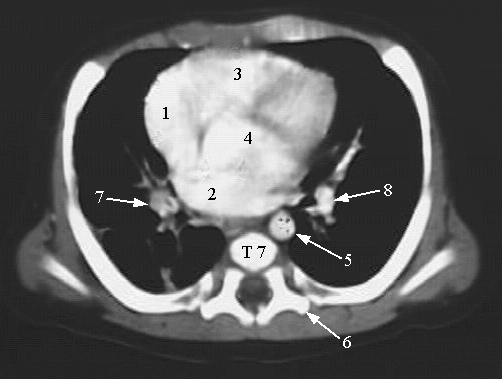

Thorax- Chest CT Heart

1. Right Atrium

2. Left Atrium

3. Right Ventricle

4. Left Ventricle

5. Descending Aorta

6. Transverse Process of T7

7. Right Bronchus

8. Left Bronchus